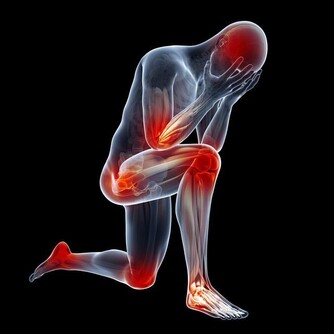

第二、促進尿酸的排泄

促進尿酸排泄的辦法,除了大家都熟悉的多喝水之外(每天喝水量不少於2000毫升),還可以多吃點鹼性食物,比如適當喝點蘇打水。

除此之外,要多運動,控制自己的體重。因為減肥和運動也是有利於降尿酸的行為。但是需要提醒大家的是,減肥需要循序漸進,切莫心急。而運動也要選擇適合自己的運動項目,根據自己的身體情況來選擇,避免運動強度過大,造成不必要的身體傷害。

如果病情較為嚴重的患者,還是要及時去醫院檢查,聽從醫生的指導,進行治療。